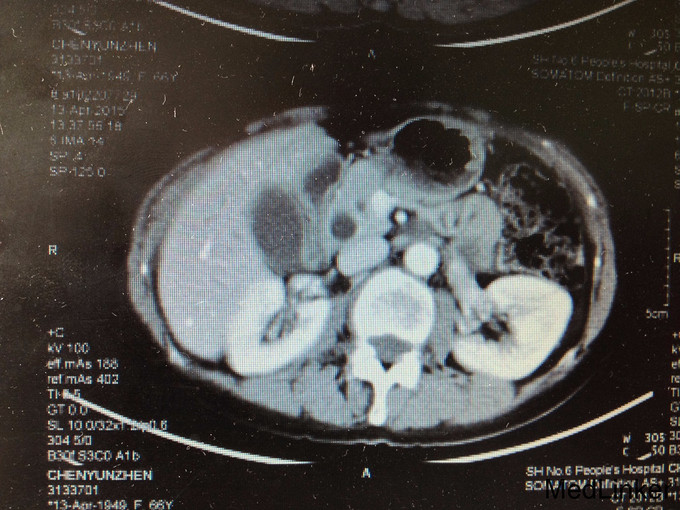

查体:皮肤巩膜无明显黄染,腹部平坦,未见明显胃肠型及异常隆起,全腹软,右上腹部压痛不明显,无反跳痛,无肌卫,无腹部反跳痛,全腹无包块,肝脏肋下未触及,脾脏肋下未触及,无肝区叩击痛,Murphy’s征阴性,肠鸣音正常,移动性浊音-。 辅查:血常规(2015-4-1):WBC:5.9×109/L,N:57.6%,RBC:4.17×1012/L,Hb:127g/L,PLT:196×109/L。肝功能:ALT:109U/L,AST:87U/L,TB:18.6umol/L。肿瘤标记物:AFP:2.7ug/L,CEA:4.71ug/L,CA19-9:37.19KU/L。 2015-4-13 上腹部MRI报告:1.胆总管下段异常信号,胆总管、胰管轻度扩张,胆总管下段结石可能大,必要时MRI增强检查,排除胆总管下段占位。2.胆囊颈结石,胆囊增大。3.附见;肝脏左叶囊性病灶。 2015-4-14上腹部增强CT报告:1.胆总管下端异常强化,结石可能,肝内外胆管及主胰管扩张,胆囊增大,必要时MRI增强进一步检查。2.肝脏小囊肿。

治疗经过:患者入院后于无明显诱因下出现右上腹疼痛,压痛明显,拒按。结合腹部CT及MRI影像学表现,胰胆管明显扩张,考虑急性胰腺炎发作。辅查:淀粉酶(干式) 1640 U/L ↑。总蛋白 61 g/L ,白蛋白 36 g/L ,白/球比例 1.4 ,谷丙转氨酶 218 U/L ↑,谷草转氨酶 183 U/L ↑,γ-谷氨酰酶 548 U/L ↑,总胆红素 13.3 μmol/L ,直接胆红素 5.4 μmol/L ,肌酐 66 μmol/L ,血清钾 4.3 mmol/L ,血清钠 142 mmol/L ,血清氯 106 mmol/L ↑。白细胞 6.3 *10^9/L ,红细胞 3.84 X10^12/L ,血红蛋白 117 g/L ,细胞比积 35.9 % ,血小板 197 X10^9/L ,中性细胞百分比 58.7 % 。甲胎蛋白(AFP) 2.68 ng/mL ,癌胚抗原(CEA) 4.99 ng/mL ,糖类抗原(CA125) 6.91 U/mL ,糖类抗原(CA199) 39.45 U/mL ↑。处理:予禁食,查血、尿淀粉酶,抑酸、保肝、补液支持治疗,经治疗后症状缓解。后因患者无黄疸,为进一步明确胆总管梗阻原因,行ERCP+ERBD+十二指肠乳头活检术。 检查治疗经过:十二指肠镜进入十二指肠,降部内侧见乳头,十二指肠乳头肿大,粘膜面外观正常,触之易出血。BOSTON-Jagwire导丝留置胰管,BOSTON-Jagwire导丝进入胆管引导COOK-FS-OMNI导管造影,胆管显影,胆管扩张,胰管造影胰管扩张。胆管胰管内未见充盈缺损。十二指肠乳头开口处取四块活检。放置辛菖猪胆道引流管(8.5F,6cm),辛菖胰管引流(F5,4cm),引流畅。结合MRI及CT考虑壶腹部占位可能。 十二指肠乳头活检病理:绒毛状腺瘤伴部分腺体重度不典型增生,局灶癌变。 患者术前诊断为十二指肠壶腹部癌,行剖腹探查,胰十二指肠切除术。术中见:见腹腔内无腹水,腹膜、盆腔内、大网膜、肝脏、肝十二指肠韧带、胰腺周围、腹腔动脉周围、肠系膜根部、腹主动脉旁等无转移性结节和肿大淋巴结。探查见此患者左右肝胆管的汇合处接近胆胰管汇合处,右侧肝胆管壁水肿增粗,十二指肠乳头部肿块大小0.3cm,行胰十二指肠完整切除。 术后病理检查报告:下半胃、胰腺、十二指肠;标本类型:切除胰腺大小 4×4×1 CM,十二指肠长 15CM,胃小弯长 8 CM,大弯长 11CM,胆囊9×3×1.5CM;肿瘤部位:肿瘤位于十二指肠乳头,大小0.5×0.3CM;组织学类型内容: 腺癌II级;血管浸润(-),淋巴管浸润(-),神经周围浸润(-);切缘: 上、下切缘及胰腺切缘均未见癌;淋巴结:以下淋巴结均未见癌转移:胰腺旁LN:0/8枚,胃大弯LN:0/6枚,胃小弯LN:0/3枚。;淋巴结免疫反应状态: SH(+), PH(+), GH(+);肿瘤旁病变: 粘膜组织慢性炎(十二指肠乳头):腺癌II级,肿瘤侵及肌层,未累及胰腺,胰腺导管扩张,小胆管增生伴中度不典型增生。(胆囊):慢性胆囊炎伴腺体增生。肿瘤组织免疫酶标记结果:CA199(-)、CEA(+)、S-100(-)、CK19(+)、CK7(+)、CDX2(-)、CK(-)、Ki67(80%+)。